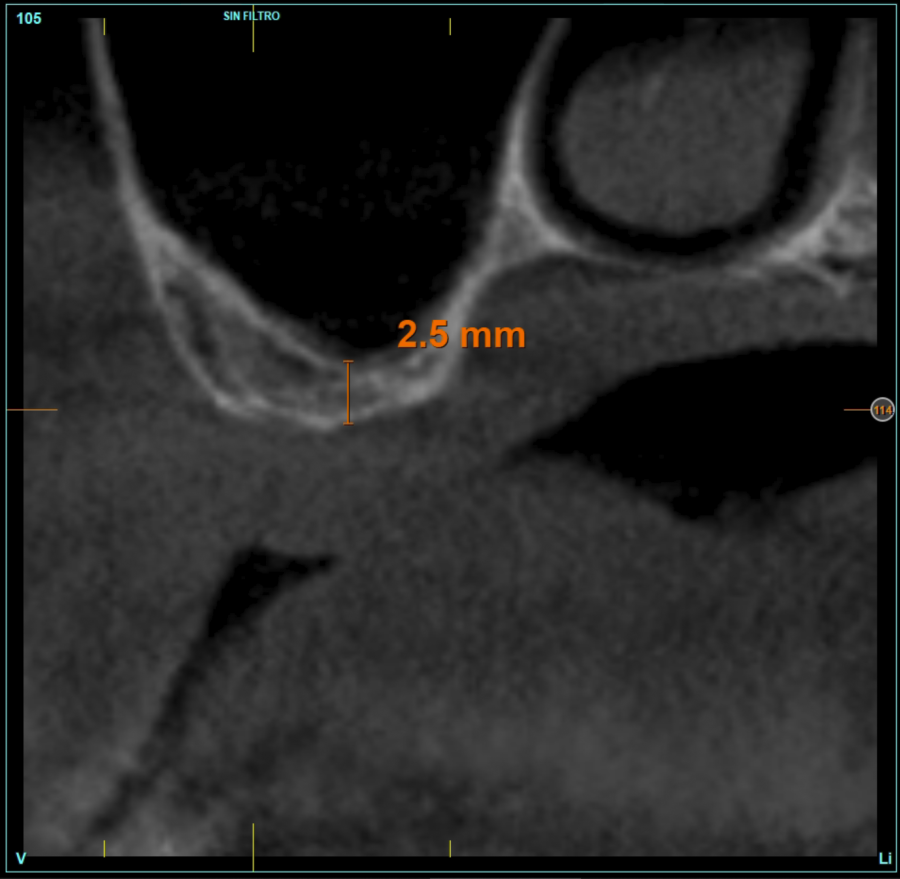

In all cases, a diagnosis was made based on study models, intraoral examination of the patient and performing a Cone-beam analysed using the specific BTI-Scan 3 software (Biotechnology Institute, Vitoria, Alava, Spain).

Patients attend subsequent check-ups performing a control Cone-Beam after 5 months (before loading the implant) and after one year of the load, performing a new measurement in these images to analyse the bone gain and the maintenance of the same. In these check-ups, data are collected on prosthetic complications or crestal bone loss in these patients, as well as possible failures.

The mean height of the residual bone volume was 3.1 mm (+/- 0.3 mm with a range of 3-4 mm). In all cases, transcrestal sinus elevation was performed, with particulate autologous bone obtained from milling the neo alveolus generation zone for implant insertion, being the average of this elevation above the apex of the implant of 2.8 mm (+/- 0.99 range 1.9 -5 mm). In the CT control scan after one year of inserting the studied implants, the bone gain achieved was maintained, no decrease in the volume gained was observed, only three cases showed a decrease of between 0.4 and 0.5 mm of the initial volume at the end (Table).

Figures 2-19 show one of the cases included in the study.